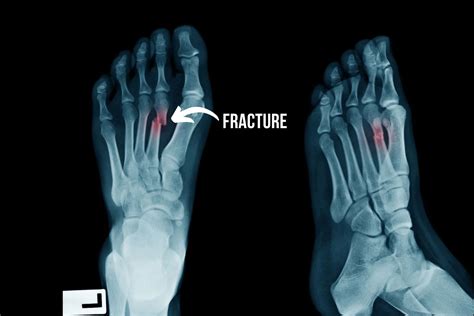

• Imaging Tests: X-rays are the most common imaging test used to diagnose fractures. However, hairline fractures may not always be visible on initial X-rays. In such cases, additional imaging tests such as MRI or CT scans may be required.

A hairline fracture, also known as a stress fracture, is a thin crack in the bone. In the case of a hairline fracture ankle, this crack typically occurs in one of the three bones that form the ankle joint: the tibia, fibula, or talus. These fractures are often caused by repetitive stress or a sudden impact, such as twisting the ankle or landing awkwardly after a jump.

Recognizing the symptoms of a hairline fracture ankle is the first step toward proper treatment. Common symptoms include: